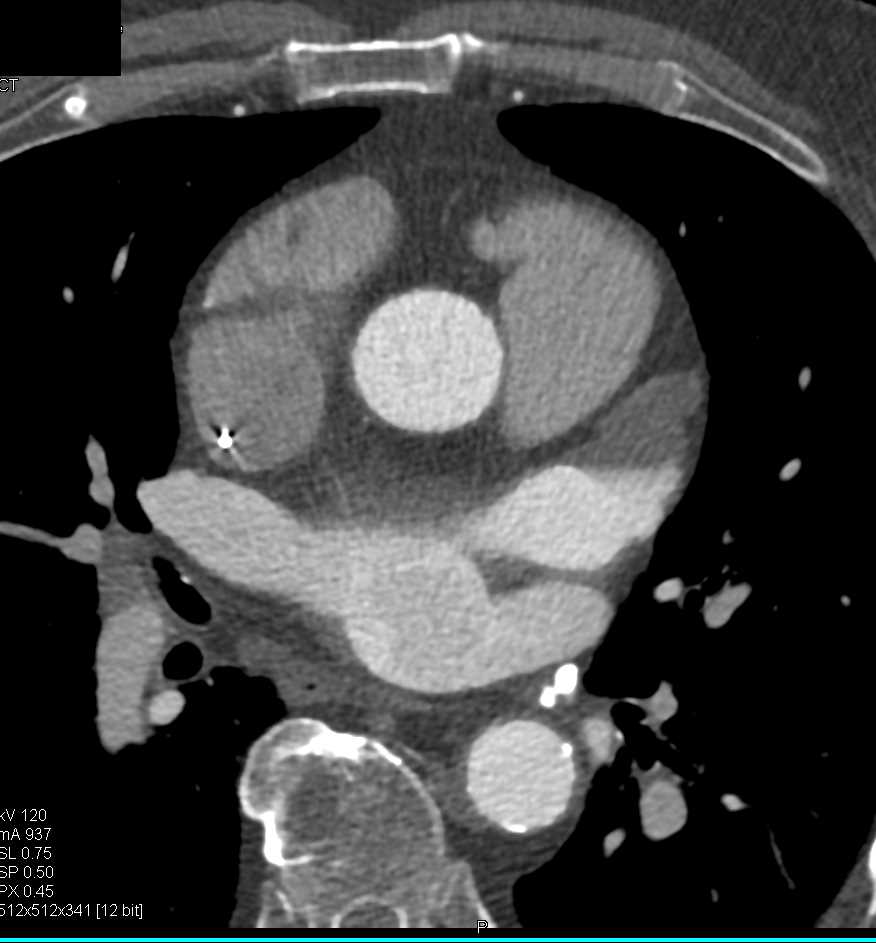

Patent Ductus Arteriosus (PDA)